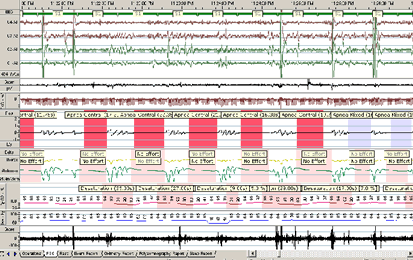

Fig. 2 - Inregistrare polisomnografica a unor episoade de apnee obstructiva;

Îngustarea cailor aeriene superioare in apneea obstructiva se realizeaza de obicei la nivel orofaringian ca urmare a prabusirii tonusului muschilor dilatatori ai faringelui, a caror contractie asigura mentinerea permeabilitatii cailor aeriene superioare in timpul inspirului. Obstructia poate fi si secundara unor malformatii mandibulare, hipertrofii amigdaliene si adenoidiene sau alterari ale partilor moi buco-faringiene din acromegalie, mixedem, obezitate.

Polisomnografia este metoda diagnostica de certitudine pentru apneea de somn; ea reprezinta un studiu al somnului nocturn, care include inregistrarea urmatorilor parametri:

- electroencefalograma, electrooculograma, electromiograma muschilor mentonieri;

- debitul aerian nazo-bucal, prin folosirea unor termistori nazali si miscarilor respiratorii prin pletismografie de inductanta, folosind centuri toracica si abdominala;

- saturatia in oxigen a sangelui arterial prin oximetrie la nivelul urechii sau degetului;

- frecventa cardica prin intermediul electrocardiogramei;

- sunetele traheale prin intermediul unui microfon;

- pozitia corpului prin intermediul unui senzor si analiza comportamentului global al pacientului prin intermediul unei camere video.

Cu ajutorul acestor elemente, se realizeaza:

- analiza stadiilor somnului,

- analiza ventilatiei,

- identificarea evenimentelor respiratorii (apnei, hipopnei) si a consecintelor lor asupra ritmului cardiac, morfologiei complexelor QRS si saturatiei arteriale a oxigenului.